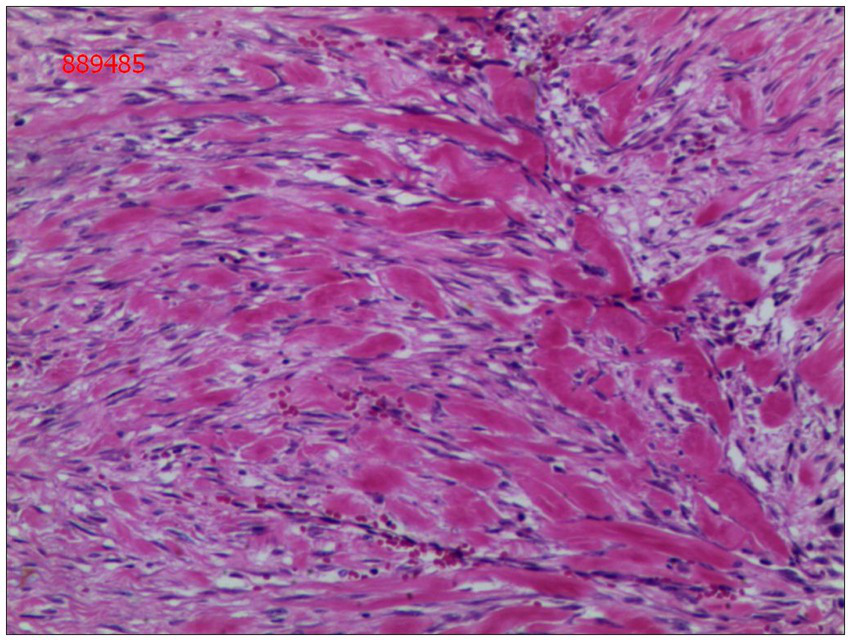

Gross examination of the resected specimen revealed a grey-white nodular mass measuring approximately 4*3*5 cm, characterized by a firm and scar-like consistency (Figure 2). Histologically, the mass extended from the submucosal layer to the serosa of the distal ileum, infiltrating and growing within the intestinal wall and adipose tissue, displaying a fascicular or woven pattern arrangement. The spindle-shaped cells exhibited abundant cytoplasm, elongated nuclei with wavy features, interspersed with collagen fibers, and minimal infiltration of inflammatory cells (Figures 3, 4).

Figure 4. Spindle cells with interspersed collagen fibers(hematoxylin and eosin; magnification ×400).